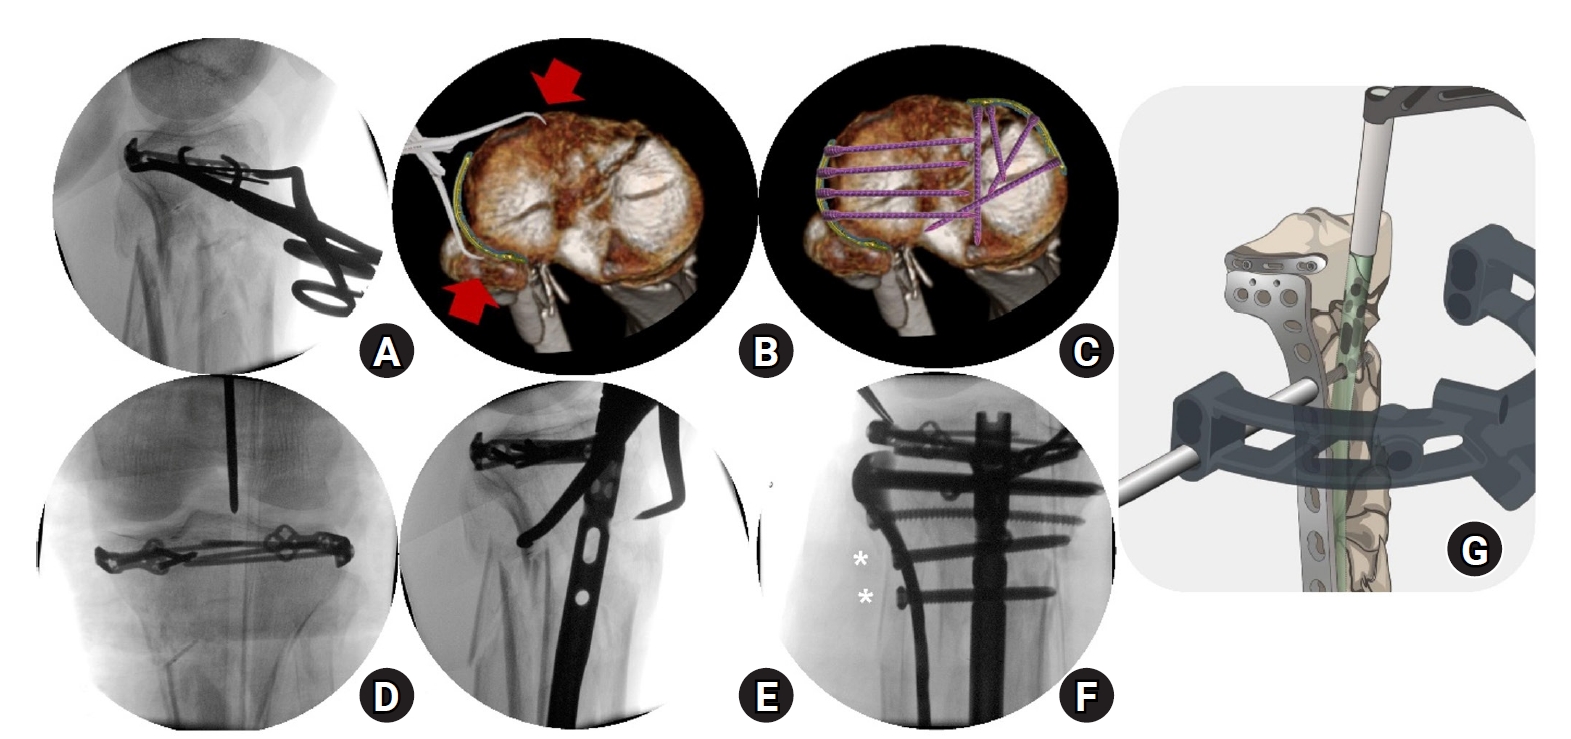

Fig. 6.

Fluoroscopic images and schematic illustrations of the rim plate-assisted intramedullary nail and plate combination technique. (A) Lateral plateau depression was elevated. (B, C) A contoured 2.7-mm variable-angle locking compression plate was applied with medial-to-lateral compression and fixed to unify the plateau into a single segment. (D) Intramedullary nailing was performed via the suprapatellar approach. (E) Alignment was confirmed with a rod. (F) A 4.5-mm proximal lateral tibia plate was added for final fixation.

jmt-2025-00290f6.jpg

Surgical technique

As in case 1, the procedure started with converting the tibial plateau fracture into a single segment using a rim plate. An anterolateral approach was chosen because of the anterolateral location of the main fracture. The patient had a lateral condylar depression of the tibial plateau, which was initially elevated using an impactor (Fig. 6A). After the elevation of the depressed fragment, Kirschner wires were temporarily fixed through the inside-out technique [9]. A 2.7-mm VA-LCP was then shaped and positioned, followed by medial-to-lateral compression using a colinear clamp (Fig. 6B). Both cortical and locking screws were inserted through the VA-LCP, which connected the plateau fragments into a single segment (Fig. 6C). A suprapatellar approach was employed for IM nailing (Fig. 6D). As in case 1, only three cancellous screws could be inserted into the proximal fragment through the IM nail. To enable immediate full weight bearing, an additional plate was applied to augment fixation, which completed the NPC technique (Fig. 6F). In this patient, the longest available 4.5-mm LCP proximal tibia plate did not provide sufficient construct length. Therefore, a 4.5-mm LCP proximal lateral tibia plate was used instead; this plate has a proximally oblique design, in contrast to the sharply angled, inverted “L”-shaped design of the standard proximal tibia plate. Postoperative plain radiographs and CT images are shown in Fig. 7.